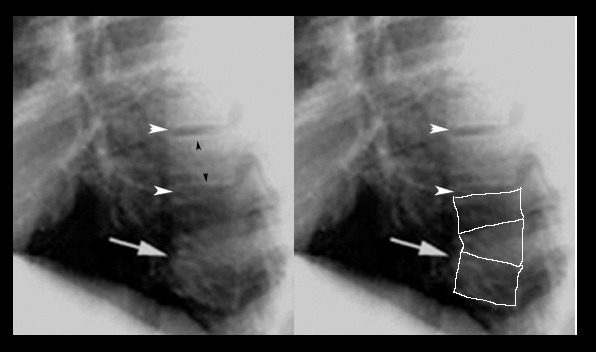

• White arrowheads point to normal intervertebral spaces.

• White arrow points to loss of the space.

• Black arrowheads point to normal end plates (white line). When infection sets in, the end plates are destroyed as the infection spreads from the joint. In malignancy, even with collapse of the vertebra, the end plates are preserved.